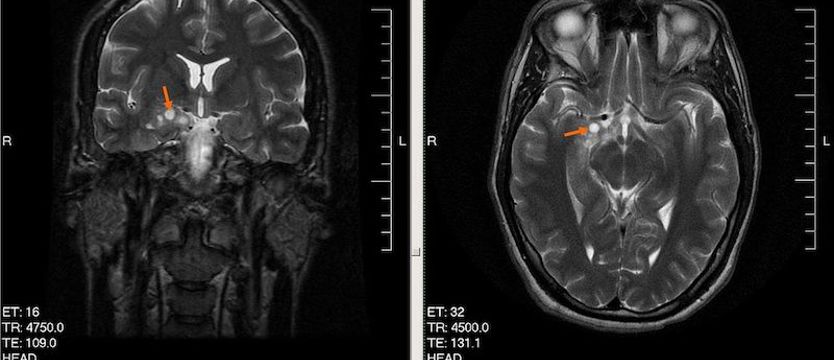

Wysokozróżnicowany glejak u 28-letniego mężczyzny Fot. Wikipedia

Na zdjęciu: Wysokozróżnicowany glejak u 28-letniego mężczyzny

Fot. Wikipedia

Dalsza diagnoza opiera się o badania obrazowe, czyli rezonans magnetyczny lub tomografię komputerową, na podstawie których rozpoznaje się guza mózgu. Są pewne cechy w obrazie diagnostycznym, które już na tym etapie pozwalają stwierdzić, że mamy do czynienia z glejakiem. Pewne rozpoznanie stawia się jednak dopiero na podstawie badania histopatologicznego, po usunięciu guza.